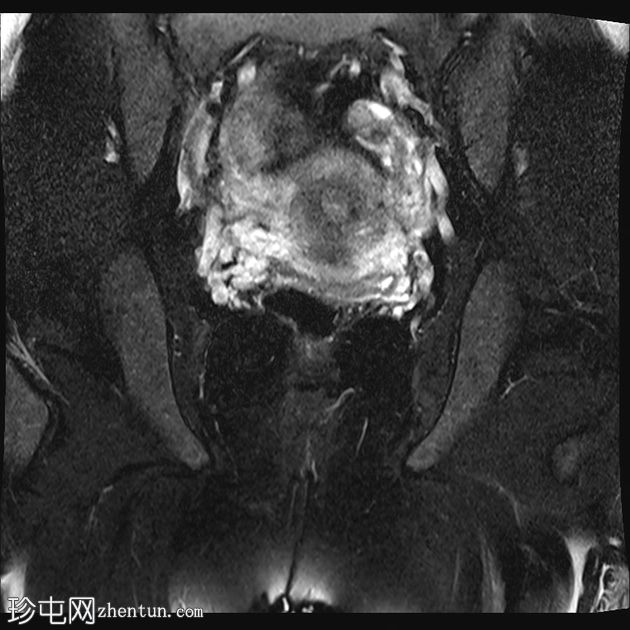

冠状位

T2加权像

MRI特征符合剖宫产术后瘢痕子宫内膜异位症,表现为特征性T1高信号伴T1FS持续存在,T2低信号伴内部高信号灶,病灶边缘浸润于腹前壁肌肉内,以及对比增强。

该病灶累及腹白线并浸润腹直肌,主要位于中线左侧,耻骨联合及结节处腹直肌起点上方。

影像学表现符合病灶内出血成分,提示既往剖宫产瘢痕处存在异位子宫内膜组织。